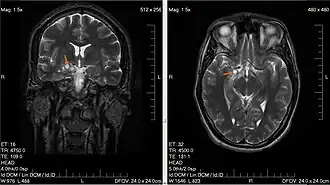

- glejak wielopostaciowy (łac. glioblastoma) – jest najczęstszym (ok. 50%) złośliwym nowotworem wywodzącym się z tkanki glejowej, rosnącym w półkulach mózgu, najczęściej w płacie czołowym i skroniowym. Obraz histopatologiczny urozmaicony, charakterystyczne są duża atypia (złośliwość histologiczna), obszary martwicy i liczne patologiczne naczynia krwionośne, które mogą stać się źródłem wylewu krwi do mózgu. Guz rośnie szybko, często szerzy się poprzez spoidło wielkie na przeciwległą półkulę mózgu (tzw. obraz "motyla" w badaniach obrazowych), może dawać przerzuty w obrębie centralnego układu nerwowego drogą płynu mózgowo-rdzeniowego lub krwionośną. Nowotwór o umiarkowanej promienioczułości. Szczyt zachorowalności to V i VI dekada życia, z niewielką przewagą mężczyzn.

- skąpodrzewiak (łac. oligodendroglioma) – rośnie najczęściej w okolicy płatów czołowych mózgu w istocie białej. Mimo powolnego wzrostu, może we wczesnej fazie rozwoju szerzyć się przez spoidło wielkie na przeciwległą półkulę mózgu (obraz "motyla" w tomografii komputerowej). W późniejszych okresach rozwoju nacieka korę mózgu i oponę pajęczą. Pod względem histologicznym opisywany jest jako przypominający wyglądem "żabi skrzek", z charakterystycznymi mikrozwapnieniami (widocznymi także na radiogramach) i licznymi naczyniami krwionośnymi. Występuje u dorosłych, dwukrotnie częściej u mężczyzn.